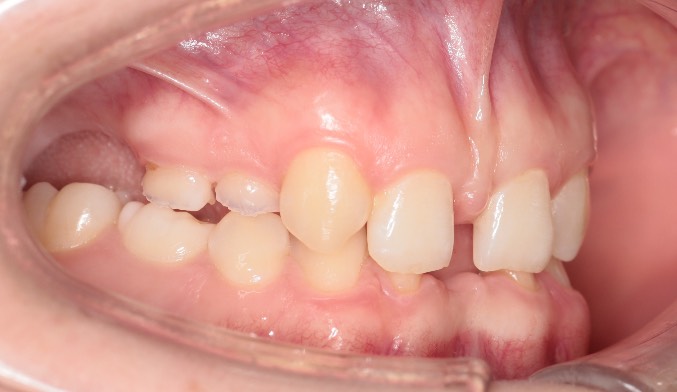

Сейчас работаю с очень редким клиническим случаем: отсутствие 11 постоянных зубов, генетически обусловленным (то есть у кого-то у родителей есть эта проблема с рождения).

Это значит, что у пациента НЕТ и НЕ будет половины зубов. На фото видны зубы, но большинство из них МОЛОЧНЫЕ, которые скоро выпадут. От того , что нет зачатков постоянных зубов происходит деформация челюстей; страдает эстетическая функция и, безусловно, пациент не может эффективно пережевывать пищу.

Пациенту 16 лет. Я рада, что пациент попал ко мне сейчас, не позднее. Все ортодонты ДО МЕНЯ отправляли еще подрасти и дождаться 18 лет, когда можно проводить имплантацию. НО❗️ я приверженец мягкого поэтапного профилактического лечения: когда мы не ждём, пока сформируется еще бОльшая патология, а потихоньку решаем маленькие проблемы. Так как чем раньше начнешь, тем легче будет создать правильную функцию и эстетику.

Мы с нашими опытными врачами собрали консилиум. Подтвердили мое предположение, что ИМЕННО сейчас ортодонт должен начать лечение, чтобы к 18 годам мы имели хорошую кость челюстей и условия для имплантации и протезирования. Работа непростая и невероятно интересная, потому что мы делаем функцию и красоту человеку, который в самом начале своего жизненного пути. Я счастлива быть причастной к этому. Пациенту понравился мой щадящий, логичный зубосохраняющий план лечения и мы начали этот путь длиною в 4 года.